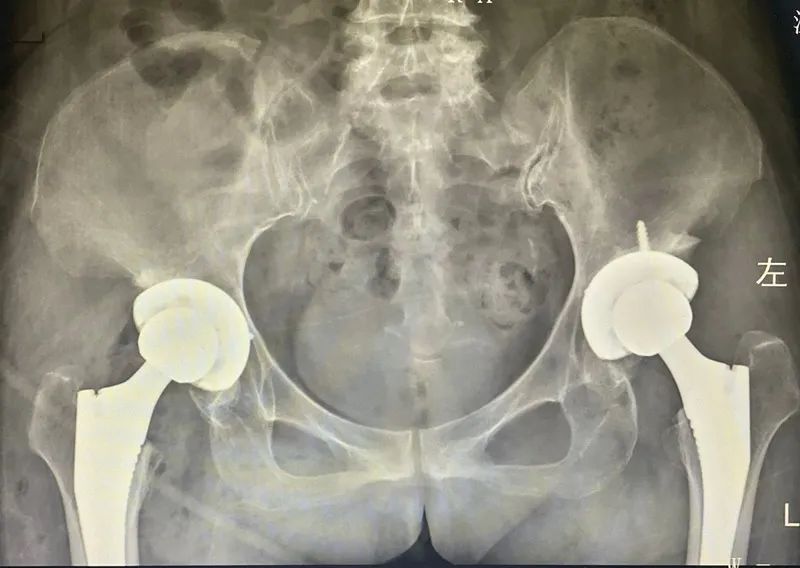

▲双侧股骨头坏死全髋关节置换术后